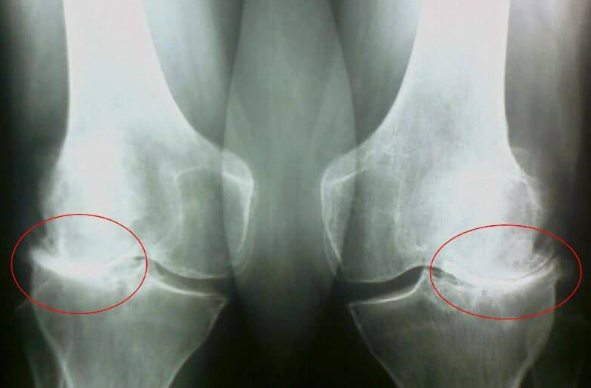

Pogledajte ove slike, možete videti da na desnoj slici nema zglobnog prostora, kosti se trljaju jedna o drugu, izazivajući jak bol. I ovaj proces je veoma teško zaustaviti! Za par godina čovek će postati invalid i neće moći da se služi.

Dr. Aleksandar Knežević: Pre svega, to su povrede i ozbiljna opterećenja. Prekomerna težina takođe stvara veliki pritisak na zglobove. Sedentarni način života, stres, obilje soli i šećera u hrani - sve to omekšava hrskavično tkivo, istroši ga i razređuje. Od svakog novog pokreta, hrskavica se briše i deformiše, kosti počinju da trljaju jedna o drugu, izazivajući nepodnošljiv bol.